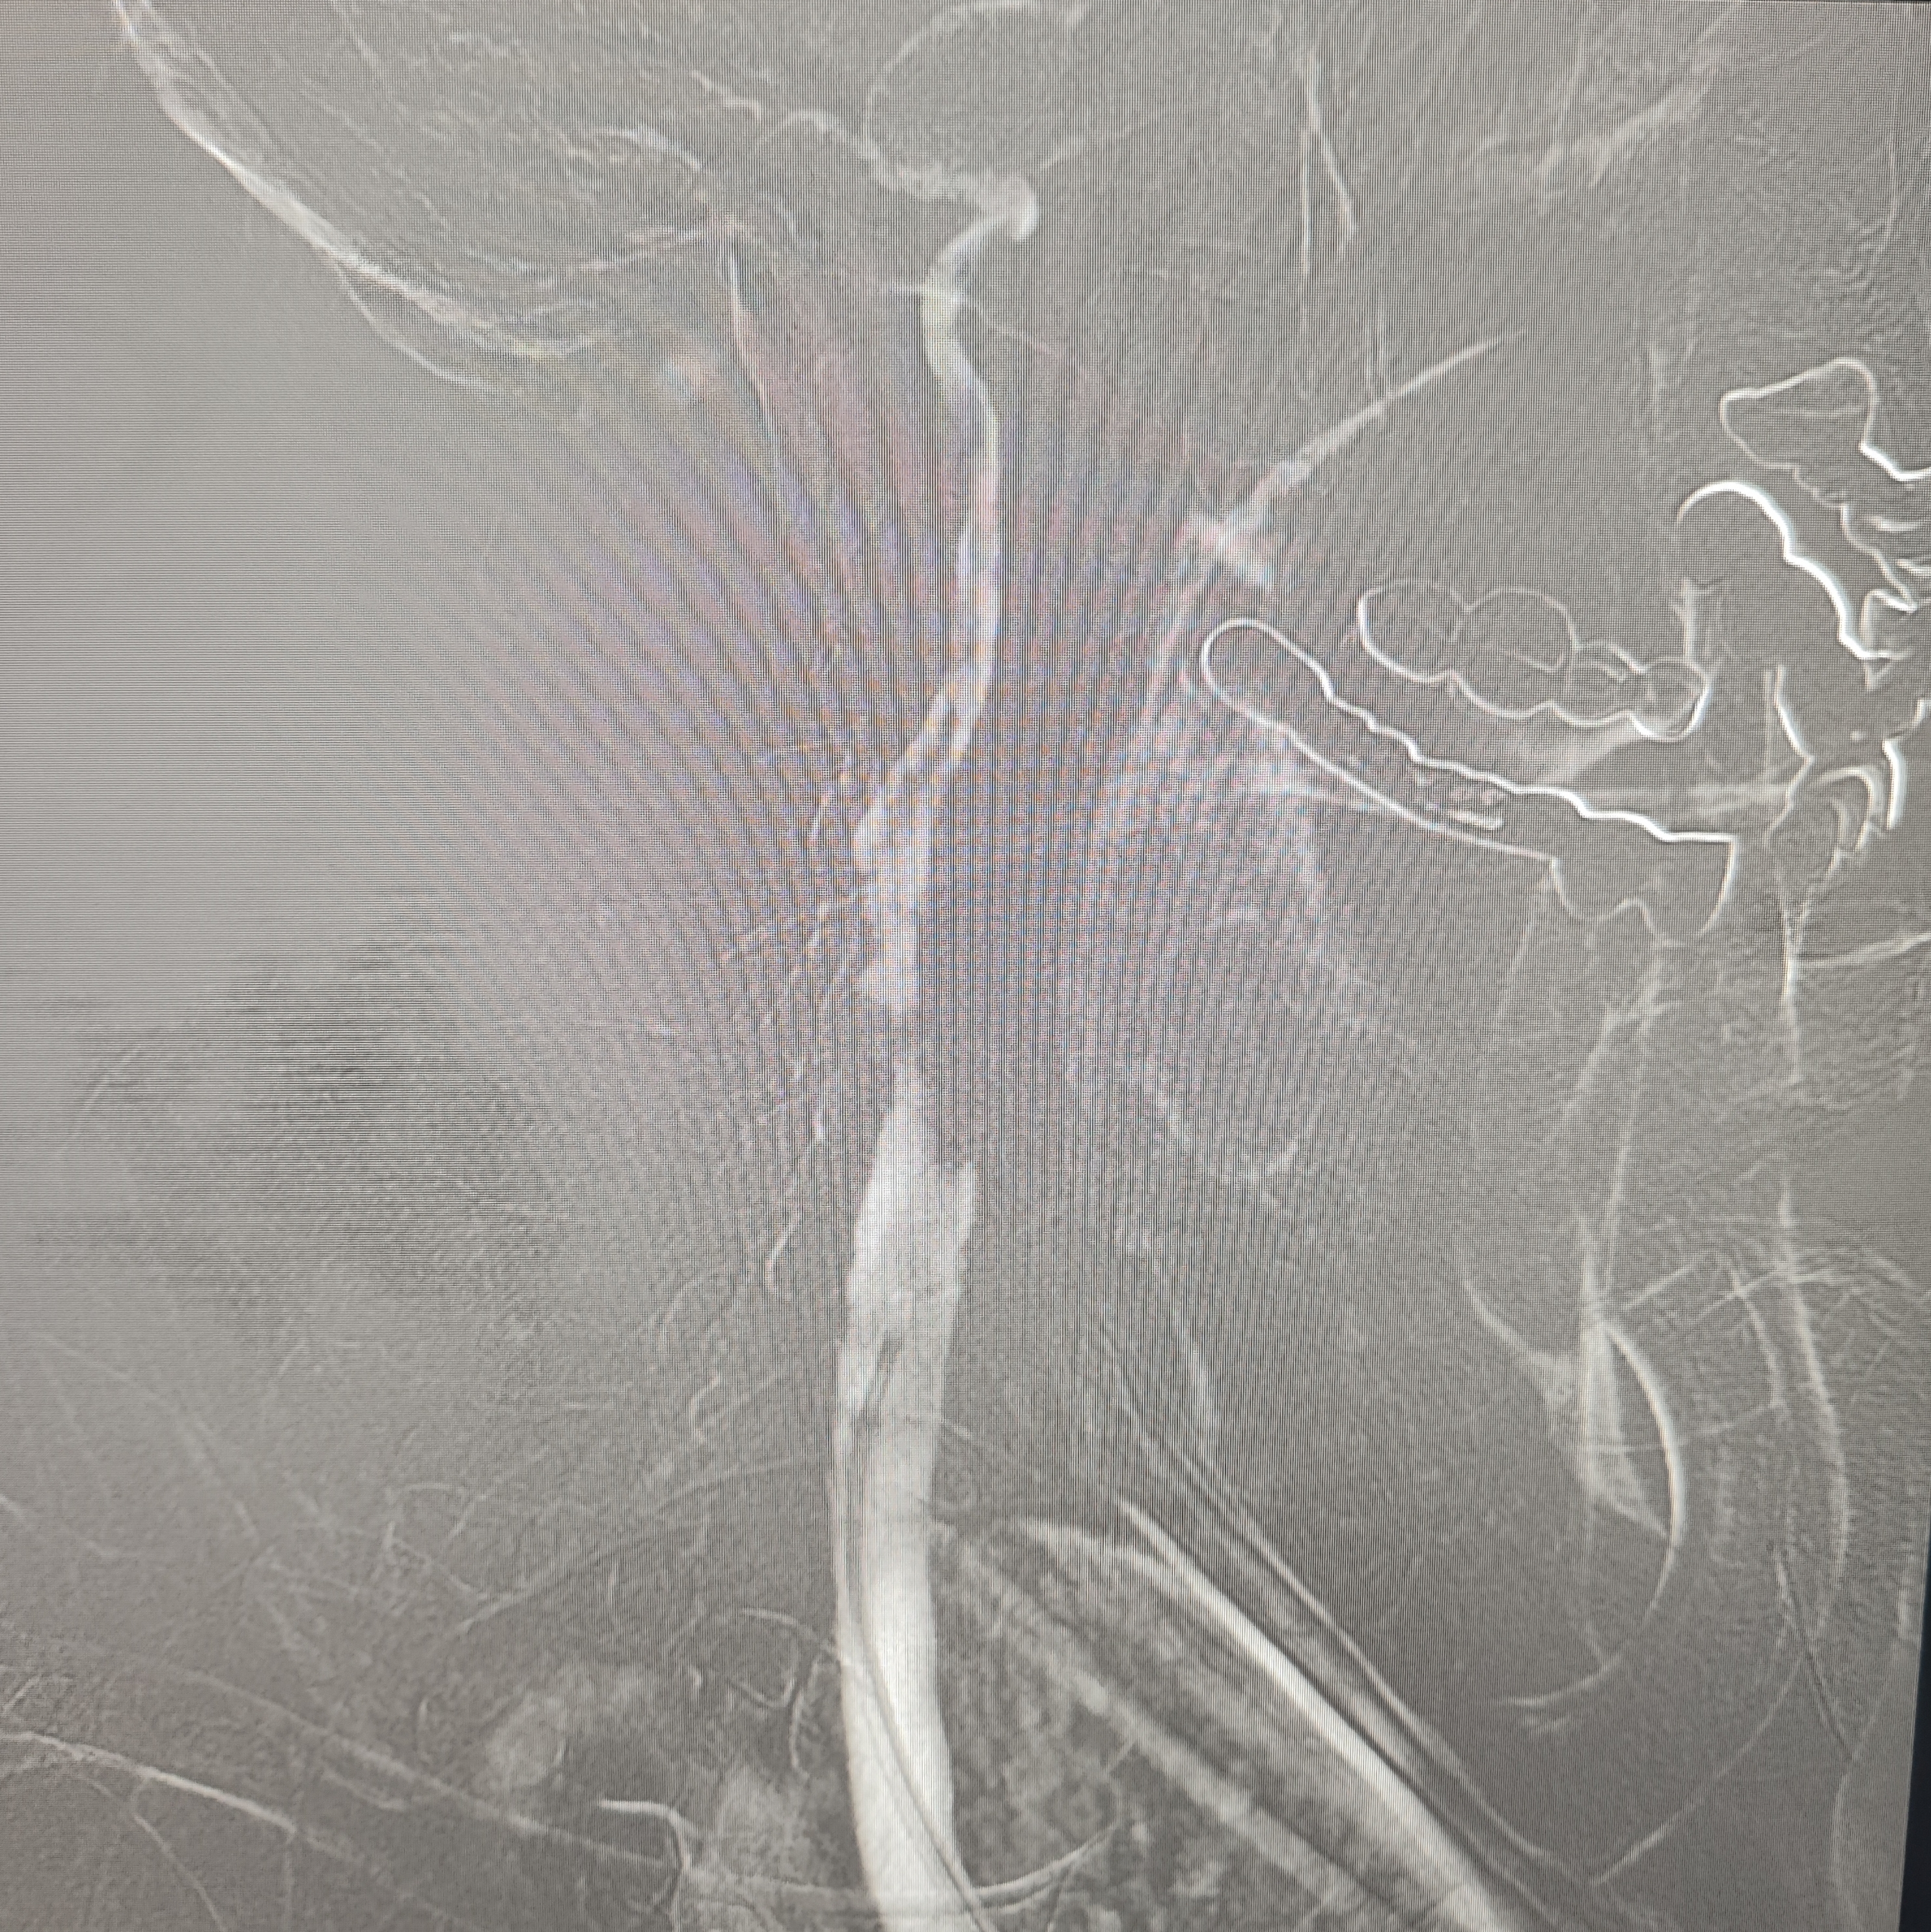

颈总巨大斑块急性闭塞的血管内治疗(双颈动脉支架桥接+支架释放后掉斑块,抽吸取栓)

84岁男性,既往右侧颈动脉狭窄病史8个月,多次脑梗未治疗,本次突发左侧肢体无力来诊,发病30小时后转入我院。

症状进行性加重,意识逐渐模糊,烦躁,左上肢肌力1级,左下肢肌力2级,当地考虑开通难度大,转入我院。

急诊上台。